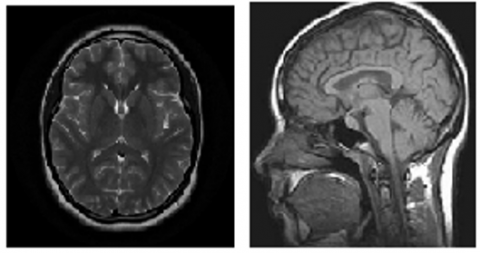

The website dataset used under the name of “Brain Tumor MRI Dataset” is (156 MB) datase comprises 7022 images of human brain MRIs that have been divided into 4 categories, as illustrated in Figure 3: glioma, meningioma, non-tumor, and pituitary. Thereafter, The MRI image dataset has been divided into two sets: a training set and a testing set. The training set contains 5,712 images, which corresponds to 81.4% of the total dataset. The remaining 18.6% of the images, which amounts to 1,311, are included in the testing set. Including subfolders for each class (glioma, meningioma, pituitary, and non-tumor), the dataset has been divided into the Training and Testing folders. There are 1,321 glioma photos,1339 meningioma pictures, 1,595 non-tumor photos and 1,457 images for pituitary in the training folder. The testing folder contains 300 images for glioma, 306 images for meningioma, 405 images for non-tumor and 300 images for pituitary as showed in Table 1.

Also, the proposed model is tested on Neurological Wholesale Hospital in Baghdad database which consists of 470 MRI image to obtain real diagnoses for real patient. It was also tested with taken website dataset.

(a) Glioma tumor

(b) Meningioma tumor

(c) Pituitary tumor

(d) Non-tumor

Figure 3. Brain tumor MRI dataset